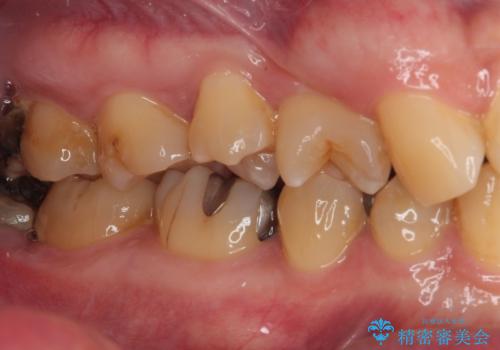

- 金属の詰め物が外れたので、虫歯の治療がしたいとのことで来院された患者様です。ほかの部位の治療などもあったため、コンポジットレジンによる応急処置を初診時に行いました。

ほかの部位の治療が一段落ついたのでセラミックインレー修復による虫歯治療を行っていくことにしました。

拡大鏡視野下でセラミックインレーに適した形に整えました。

歯と歯の間の虫歯をコンポジットレジンや保険のメタルインレーで治すと段差ができたりして清掃性が悪くなるので、セラミックインレー修復やゴールドインレー修復などの適合の良い詰め物で治療することをオススメします。